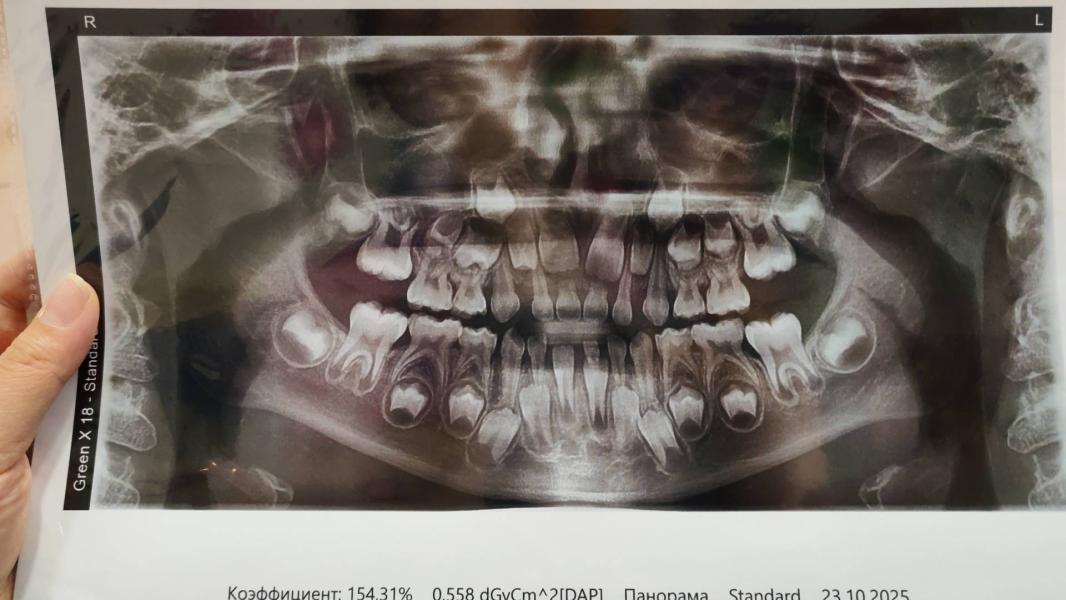

7 зубов , два из них удаления , Один восстанавливали

Наркоз 1.5 часа

68 т